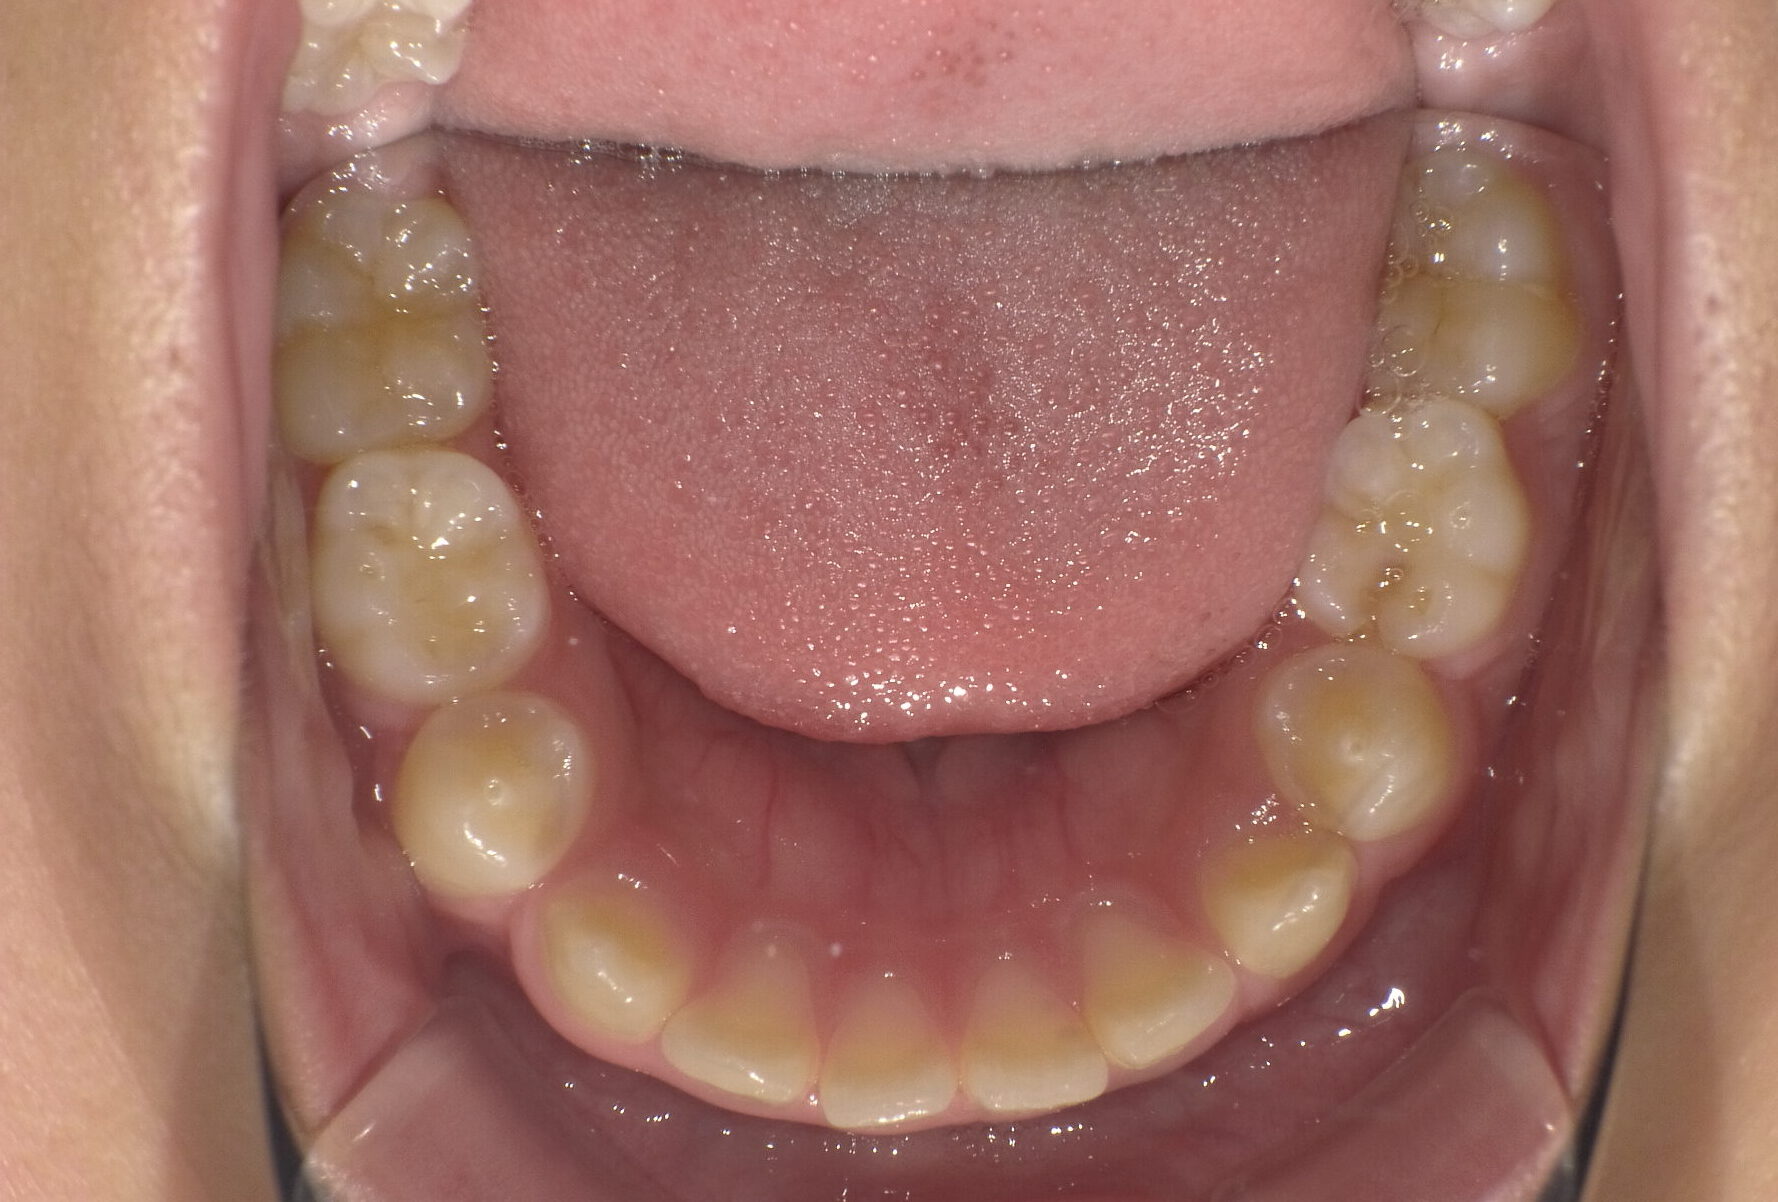

治療前

治療後

骨格:上下あごともに前方に出やすい傾向(上下顎前突)

歯並び:前歯の前方への突出(出っ歯傾向)

成長を利用した1期治療にて、マウスピース型装置や矯正装置を用い、歯並びと口元のバランスの改善を行いました

・成長期を活かし、口元の突出感を改善

・歯並びだけでなく、横顔(Eライン)にも配慮